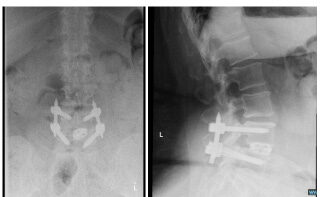

X-rays L4/5 spondylolithesis (step-off of the spine). The blue-line drawn on the right x-ray shows how the L4/5 vertebral bodies are not aligned, while the rest of the spine is aligned.

X-rays showing the same patient after a minimally invasive transforaminal lumbar interbody fusion (MIS-TLIF). The prior step-off of the spine is corrected.